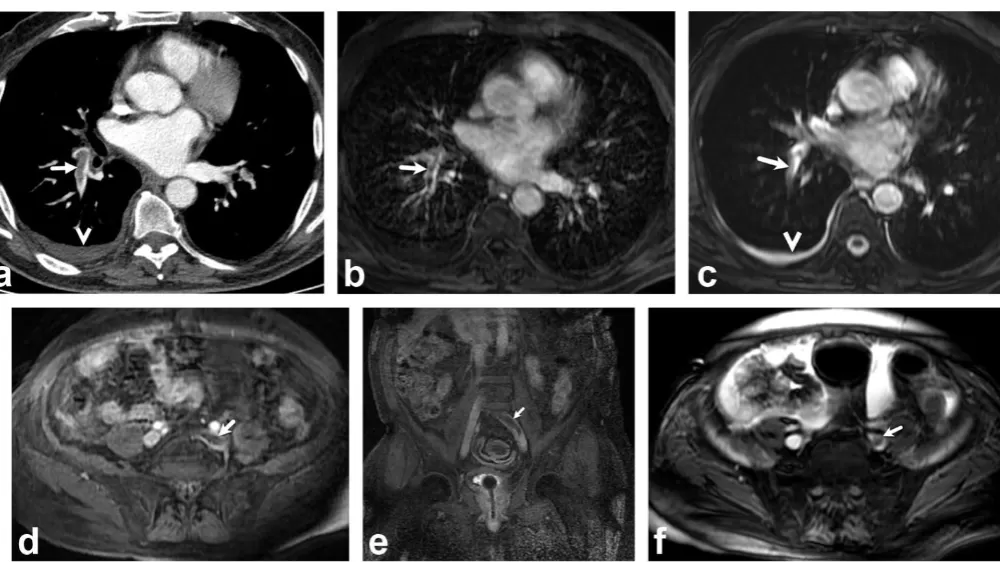

Bir dönem Denizli Tekden Hastanesinde de çalışan ve çalışmalarına ABD’de devam Dr. Nevzat Karabulut ve ekibinin yaptığı, British Journal of Radiology dergisinde yayımlanan "Diagnostic performance of contrast-enhanced and unenhanced combined pulmonary artery MRI and magnetic resonance venography techniques in the diagnosis of venous thromboembolism" başlıklı araştırmada manyetik rezonans (MR) yöntemi kullanılarak hem akciğer damarlarının hem de pıhtının kaynağı olan bacak toplardamarlarının aynı anda, tek bir incelemede değerlendirilebileceği gösterildi. Toplam 44 hastanın incelendiği çalışmada elde edilen sonuçlar oldukça dikkat çekti.

Kontrastlı MR yöntemi, hastaların tamamında akciğer embolisini doğru şekilde tespit ederken; kontrastsız MR yöntemi de yüksek doğruluk oranına ulaştı ve önemli ölçüde güvenilir sonuçlar verdi. Bu bulgular, radyasyon içermeyen MR yönteminin pıhtı hastalığını saptamada güçlü bir alternatif olduğunu ortaya koydu. Özellikle Radyasyon riskinin daha önemli olduğugenç hastalarda ve gebelerde MR’ın güvenli ve etkili bir seçenek olabileceği vurgulandı.

Uluslararası literatürde yankı uyandıran çalışma hakkında bilgi veren Dr. Nevzat Karabulut, "Akciğer embolisi, genellikle bacak damarlarındaki pıhtının dolaşımla akciğer damarını tıkaması sonucu oluşan ve zamanında fark edilmediğinde hayati tehlike oluşturabilen acil bir tıbbi durumdur. Bugün bu hastalıkları teşhis etmek için en sık Radyasyon içeren ilaçlı bilgisayarlı tomografi (BT) anjiyografisi kullanılıyor. Ancak Radyasyon ve kullanılan kontrastlı madde özellikle hamileler, genç hastalar ve kontrast maddeye alerjisi olan kişiler için risk oluşturabilir. Bu nedenle doktorlar radyasyon içermeyen ve daha güvenli alternatif yöntemler üzerinde çalışmaktadır. Ekibimle birlikte yapılan bilimsel çalışmanın büyük uluslararası araştırmalarda kaynak olarak gösterilmesi, o çalışmanın ne kadar değerli ve etkili olduğunu gösterir. Bu durum, yapılan araştırmanın sadece yayımlandığı dönemde değil, uzun vadede de bilim dünyasına katkı sağladığını ortaya koyar" dedi.